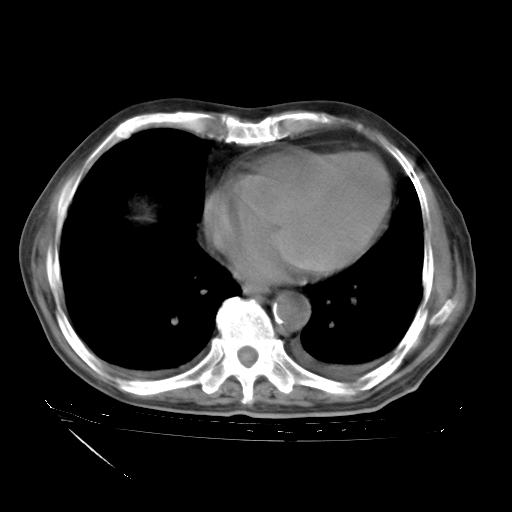

甲强龙80mg/日+抗结核治疗(异烟肼+利福霉素+乙胺丁醇)10天。复查肺部CT。

治疗10天肺部CT